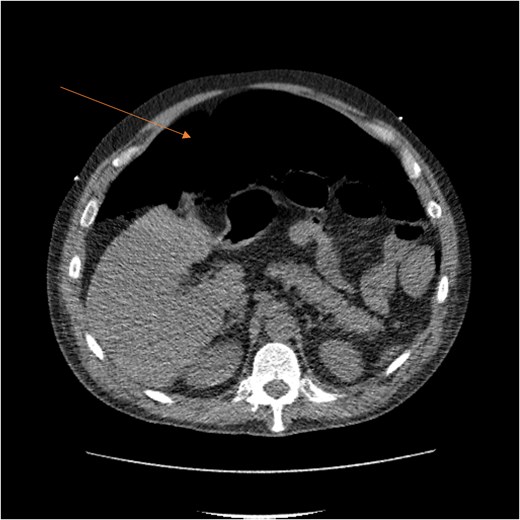

A massive transfusion protocol was initiated, and the patient received four units of packed red blood cells, six units of fresh frozen plasma, two units of platelets, and bicarbonate boluses. A CT abdomen and pelvis was performed to reassess the RSH, revealing an interval enlargement (15.3 × 10.7 × 20.4 cm) with a focal blush at the inferior portion, concerning for active extravasation (Fig. 3). The patient was hemodynamically stabilized and underwent inferior vena cava (IVC) filter placement once his hemoglobin reached 8 g/dl.